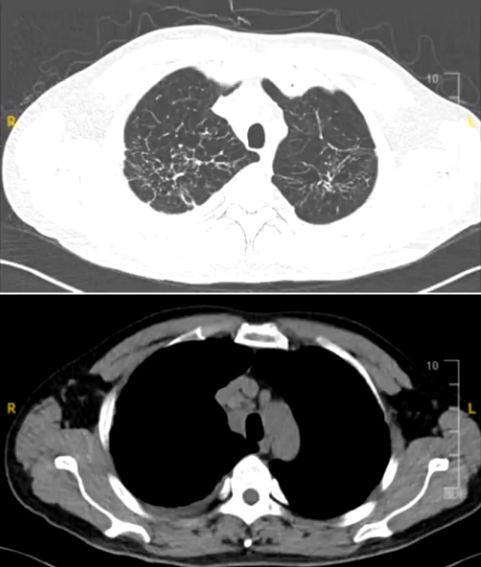

胸部CT:双肺弥漫边界不清的微结节浸润和囊腔样改变,肺门及纵隔多发增大淋巴结。

但胸部CT显示两肺弥漫微结节浸润和囊腔样改变,符合朗格汉斯细胞组织细胞增生症影像学表现,且肺门和纵隔多发淋巴结增大。全身PET-CT检查发现垂体柄增粗,SUV值轻微升高,右侧锁骨区、主动脉旁和双肺门淋巴结增大伴低代谢增高。考虑朗格汉斯细胞组织细胞增生症不能除外。